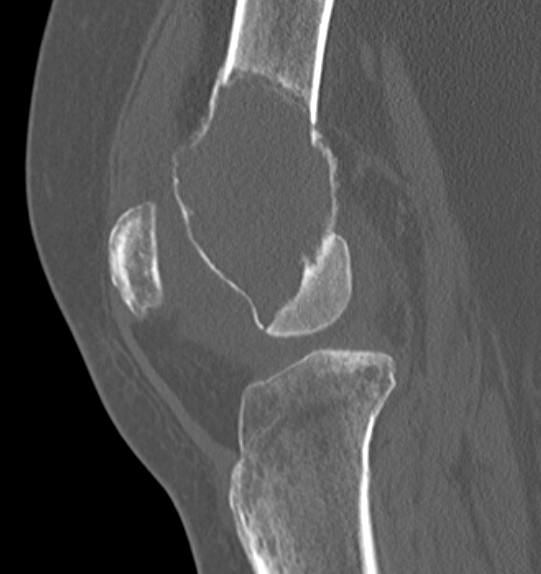

X-ray

Eccentric, sharply demarcated lytic lesion

- no sclerosis around lesion

- narrow zone of transition

- metaphysis, extending into epiphysis

- no mineralization

CT